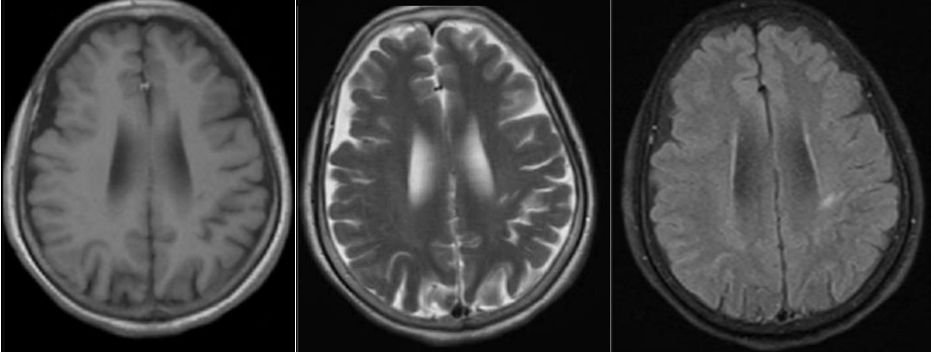

答案:抗Hu抗体相关副肿瘤综合征。补充检查:抗Hu抗体阳性,胸部CT可见一个小结节存在,余无异常。中年女性患者,亚急性起病,双下肢麻木、行走不稳,肌力有减退,二便障碍。影像学见双侧半卵圆中心、脑干及脊髓长节段病变。结合病史、查体及影像考虑脱髓鞘、免疫及肿瘤代谢性疾病。患者CSF白细胞280,一般实验室检查无异常排除感染。好多老师看到了脑室旁髓静脉样条纹,考虑为自身免疫性GFAP星形细胞病。该病早期称为慢性或亚急性激素反应性非血管炎性自身免疫炎症性脑膜脑炎。病程也有类似,通常40岁女性以上易发,急性或亚急性起病,呈进行性加重或复发-缓解病程,临床表现多样,包括发热头痛,脑病,脊髓炎,视力异常,锥体外系症状,共济失调,自主神经功能障碍等。但是该病CSF检查白细胞数增多,蛋白升高,寡克隆区带阳性。脑脊液和血清中检测到GFAP抗体可确诊。影像特征性表现为垂直于脑室的脑白质血管周围线样放射状增强。

还有多数老师考虑脱髓鞘病,CSF蛋白较高,余正常,影像表现也不符合脱髓鞘病的特点,亦排除脱髓鞘疾病。对于脊髓病变,诊断思路如下: